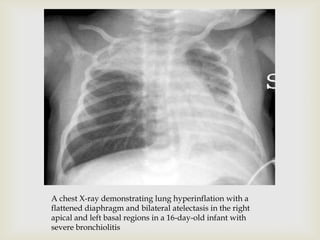

 DIAGNOSIS

 Chest X-ray

 Hyperinflation, increased lucency and

increased bronchovascular markings and mild

infiltrates

A chest X-ray demonstrating lung hyperinflation with a

flattened diaphragm and bilateral atelectasis in the right

apical and left basal regions in a 16-day-old infant with

severe bronchiolitis